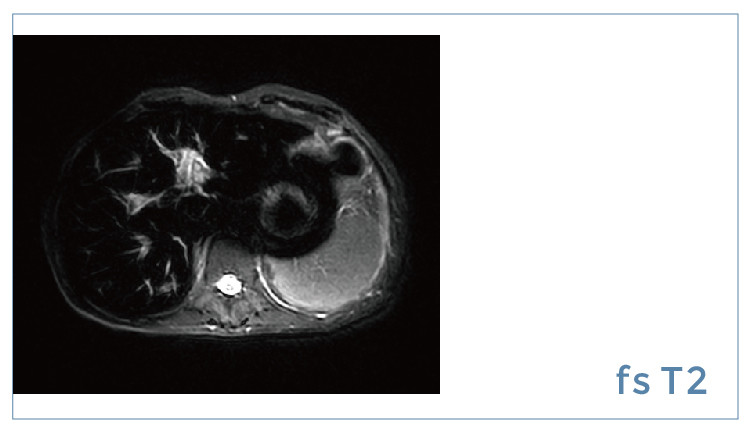

【朗润影像档案】20190914磁共振影像病例结果讨论